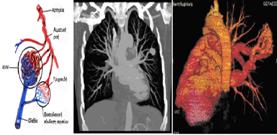

Pulmonary arteriovenous malformations and hereditary hemorrhagic telangiectasia (Rendu- Osler- Weber syndrome)

Gketsi Vasiliki, Kyrochristou Electra, Vlachou Georgia, Tsoutsinos Alexandros, Apostolopoulou Soteria

AVP= Amplatzer vascular plugs

Rendu-Osler-Weber.